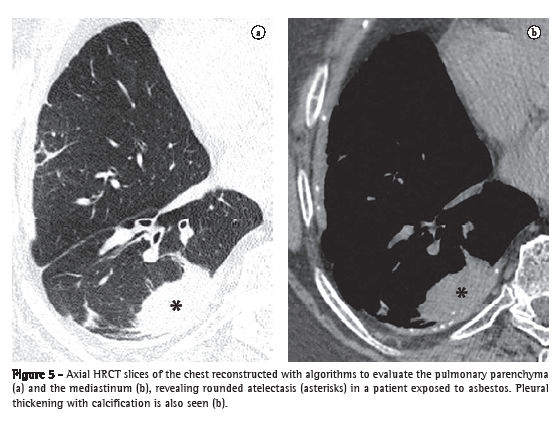

Rounded atelectasis (atelectasia redonda)Rounded atelectasis is a type of oval-shape atelectasis caused by the adherence of the adjacent lung parenchyma to the area of pleural thickening, for example, in cases of asbestos-related pleural disease or empyema resolution.(15) It manifests as a rounded focal opacity to which bronchovascular structures converge (comet tail artifact) with a pleural base near the area of pleural thickening (Figure 5).(16,17) It presents homogeneous enhancement when iodinated contrast material is used.